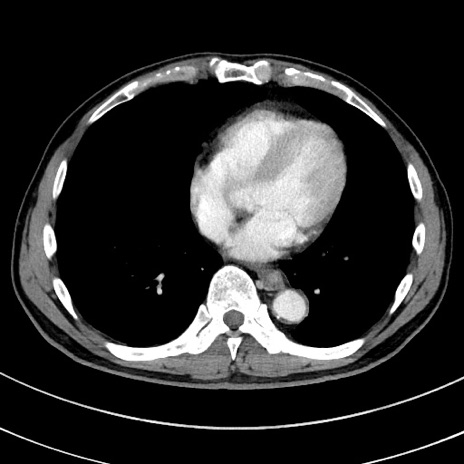

症例8(横断像)

【症例】 60歳代男性

【主訴】 黒色吐物

【現病歴】 4日前から嘔気自覚、2日前の朝食後にも嘔気あり、自分で手で嘔吐反射起こし嘔吐したところ血が混ざっていたため受診。

【既往歴】 5年前汎発性腹膜炎を伴う急性虫垂炎で手術、高血圧、前立腺肥大症、高脂血症

【身体所見】 腹部正中に手術癩痕あり 腹部平坦・軟圧痛なし膨満感あり

【データ】WBC 8400、CRP 4.54